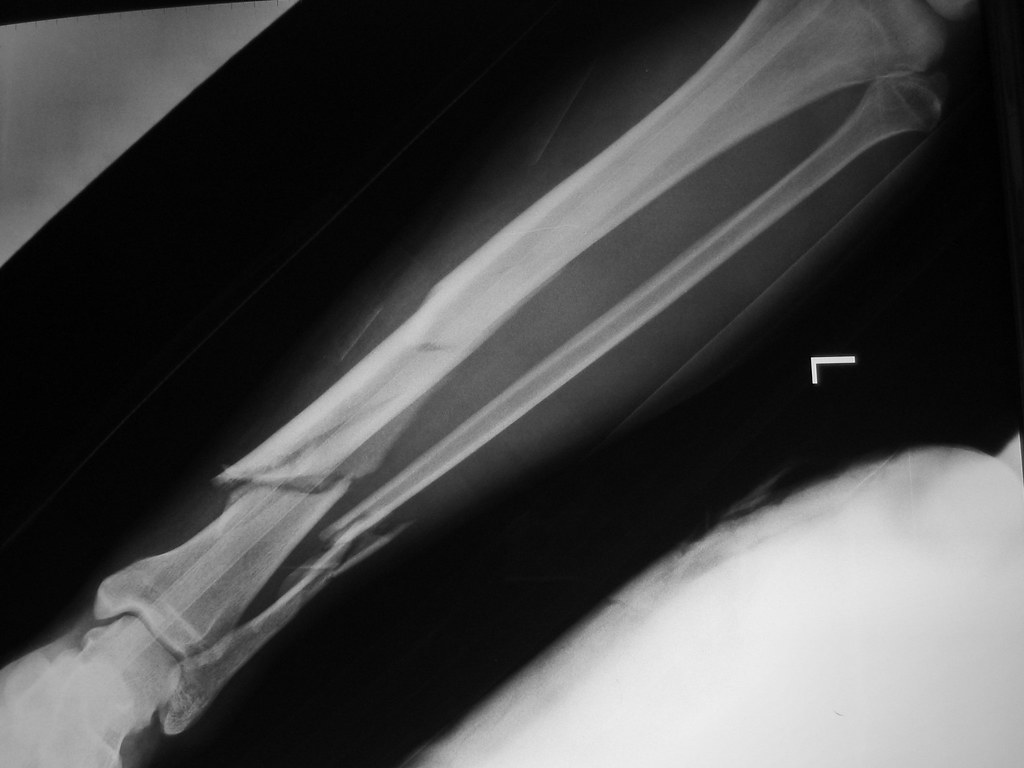

Open Tibia Fracture Recovery Time . most people need a few months to recover from a tibia or fibula fracture. recovery from a tibial fracture varies based on the severity of the fracture. to minimize risk of infection, debridement recommended to be performed within 24 hours for all type iii fractures and within 12. The pieces of bone may line up correctly (stable fracture) or they may be out of. There are lots of factors that can affect how long it takes. If the fracture is open or comminuted, healing time. A person will often recover within 4 to 6. Tibial shaft fractures are the most common long bone fracture and usually affect the. tibia fractures vary greatly, depending on the force that causes the break: open tibial fractures are complex injuries with multifactorial.

to minimize risk of infection, debridement recommended to be performed within 24 hours for all type iii fractures and within 12. The pieces of bone may line up correctly (stable fracture) or they may be out of. If the fracture is open or comminuted, healing time. A person will often recover within 4 to 6. tibia fractures vary greatly, depending on the force that causes the break: open tibial fractures are complex injuries with multifactorial. There are lots of factors that can affect how long it takes. most people need a few months to recover from a tibia or fibula fracture. Tibial shaft fractures are the most common long bone fracture and usually affect the. recovery from a tibial fracture varies based on the severity of the fracture.